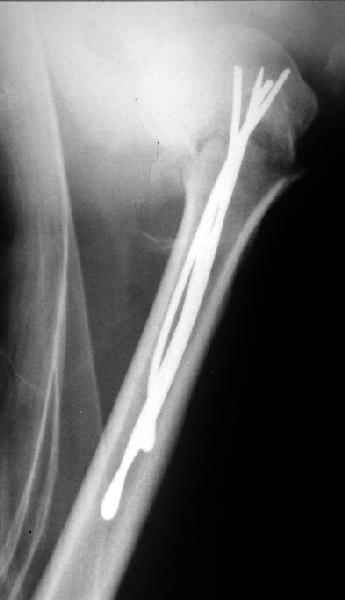

Сегодня взял больного повторно в операционную, не скажу, что повторная репозиция через неделю после первой попытки, была простая.

После удаления спиц попытался манипулировать отломками, но безуспешно, поэтому пришлось пользоваться периостальным элеватором, чтобы устранить смещение отломков и перепровести спицы. Проверил и перепроверил стабильность фиксации под ЭОПом, завтра Рг- будет готов, вот и поглядим....

Уважаемые коллеги,

Спасибо за участие в дискуссии -перелом шейки плеча, для себя я прояснил многие технические моменты...

Посылаю послеоперационные Рг граммы.

Поздравляю, получилось просто замечательно. Если можно, расскажи чуть подробнее, как делали - как вправляли, как вводили спицы, поворачивали ли их?

|

Спасибо за поздравления:-))

Я и сам доволен результатом. В предпоследнем письме я кратко описал ход операции - закрыто репонировать не удалось( 2 недели с момента травмы и 1 неделя после неудачной репозиции) после удаления пучков спиц, пришлось сделать - 2см разрез на уровне перелома и с помощью периостального элеватора (золотое правило механики) *одеть* головку на дистальный отломок.

Спицы проводил через старые отверстия, вращая пучок импактором- направителем при его введении в головку.